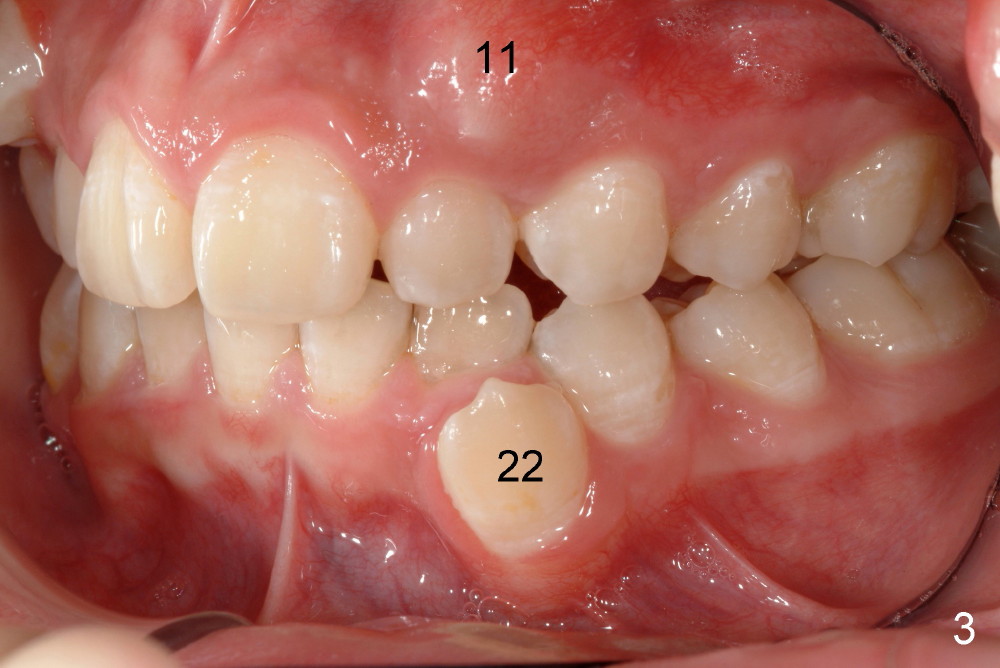

Please extract 5 and 12 in the maxilla, AND #22 in the mandible.  Yes, that is correct.  For a variety of reasons I am choosing to remove this tooth, i.e., mechanical advantage, less risk of bite opening, etc.  I also gave thought to extraction of #23 instead of #22 but the root length also points to the canine for extraction.  Bottom line, nothing made me NOT willing to extract #22, under these special circumstances.  Call me if you would like to discuss.

I hated to extract his lower left canine, more due to expected difficulty.  Amazingly, the patient was more ready for extraction than me.  He said that the tooth was not of use at all.  He has been under my care periodically for a while.  Her mom did not want to have treatment for his deciduous teeth.  Besides, he is my daughter's classmate.

In fact, the canine was easier to be extracted than the two upper first bicuspids.  It had been nonfunctional, out of occlusion.  The periodontal ligament must be loose and alveolar bone is immature.  The buccal bony plate is thin and low.  Toby returned for cleaning 3 days post extraction.  The three sockets healed so well that photos were taken.  Unfortunately the latter are misplaced.  Otherwise we would share them with you.